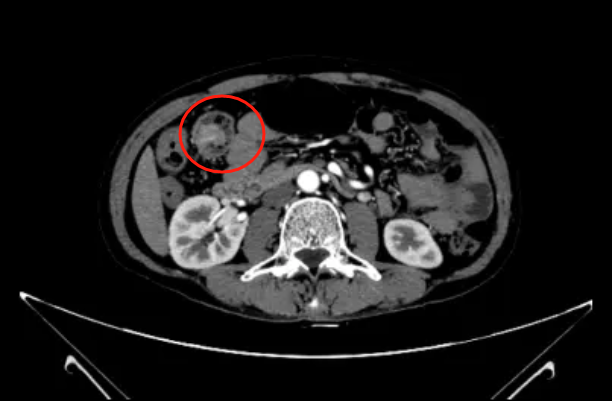

通过进一步检查发现,冯先生肠道内 多发占位,考虑 肿瘤性病变。其中升结肠见环腔肿物基本占据整个肠腔,直乙交界处巨大肿物侵犯膀胱。

升结肠肿瘤

肿瘤位置 CT